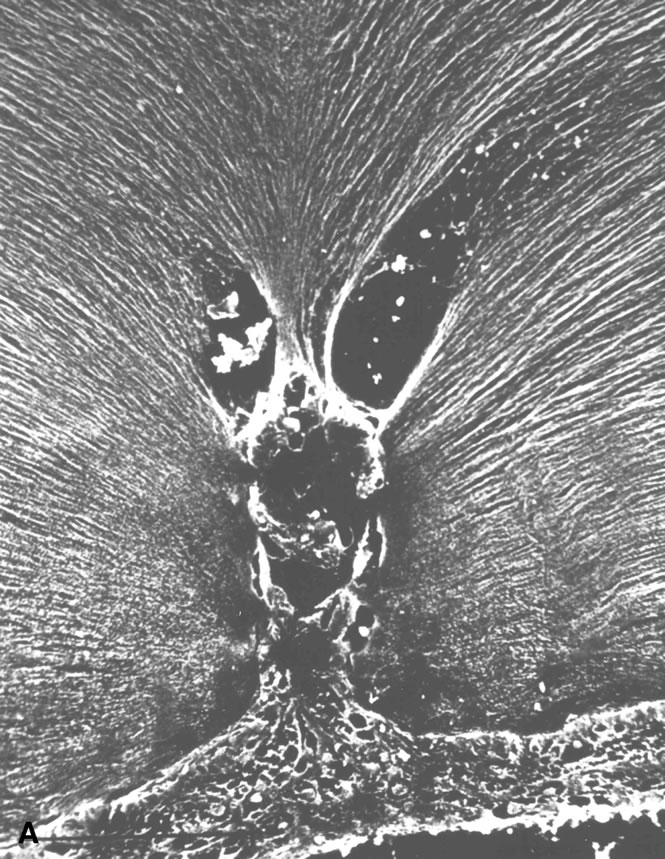

Central Vitreous

During postnatal development, there is a transition from a dense, highly light-scattering structure (Fig. 5), because at birth vitreous is mostly collagen, to homogeneous transparency that results when HA “swells” and spreads collagen fibrils apart (Fig. 6). The redistribution of HA and collagen during maturation to the adult results in the aggregation of collagen fibrils into packed bundles of parallel fibrils that appear as fibers. During the latter decades of life, these fine parallel fibers in the central vitreous become thickened and tortuous (Fig. 7). Immediately adjacent to these coarse structures are areas with little or no light-scattering properties that are filled with “liquid” vitreous. When advanced, this vitreous degeneration forms large pools of liquid vitreous identified clinically as “lacunae” (Fig. 8). When the posterior vitreous detaches from the retina, there is an overall reduction in the size of the vitreous body due to the collapse (syneresis) that occurs when liquid vitreous enters the space posterior to the vitreous cortex and anterior to the retina. This displacement of liquid vitreous occurs by way of the prepapillary “hole” and possibly the premacular vitreous cortex, and is important in the pathogenesis of posterior vitreous detachment.

Fig. 5. Vitreous structure in a human embryo at 33 weeks of gestation. The posterior aspect of the lens is seen below. The vitreous body is enclosed by the dense, highly light-scattering cortex. Parapapillary glial tissue was torn away during dissection and hangs from the prepapillary vitreous cortex. Within the vitreous body, Cloquet's canal arcs from the prepapillary vitreous toward the lens. Since its course undulates through the vitreous body, not all of Cloquet's canal can be visualized in a single horizontal section. (Sebag J: Age-related changes in human vitreous structure. Graefes Arch Clin Exp Ophthalmol 22:89, 1987. Specimens courtesy of the New England Eye Bank, Boston, MA.)

Fig. 6. Human vitreous structure during childhood. This view of the posterior and central vitreous from a 6-year-old child demonstrates a dense vitreous cortex with hyalocytes. There is vitreous extrusion into the retrohyaloid space through the premacular vitreous cortex. However, no fibers are present. (Sebag J: The Vitreous: Structure, Function and Pathobiology, p 79. New York, Springer-Verlag, 1989.)

Fig. 7. Fibrous structure of human vitreous during old age. The vitreous body of an 88-year-old woman has undergone substantial degeneration in the fibrous structure. Fibers are thickened and tortuous. The entire vitreous body appears to have undergone dissolution with empty spaces adjacent to the thickened fibers. (Sebag J: Age-related changes in human vitreous structure. Graefes Arch Clin Exp Ophthalmol 22:89, 1987. Specimens courtesy of the New England Eye Bank, Boston, MA.)

Fig. 8. Human vitreous lacunae in old age. The central vitreous has thickened, tortuous fibers. The peripheral vitreous has pockets devoid of any structure. These contain liquid vitreous and correspond to lacunae as seen clinically on biomicroscopy. (Sebag J, Balazs EA: Human vitreous fibres and vitreoretinal disease. Trans Ophthalmol Soc UK 104:123, 1985.)